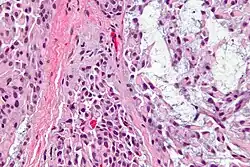

Micrograph of a myoepithelioma. H&E stain.

The myoepithelial cells may be spindled, plasmacytoid, eithelioid or clear. Tubules or epithelium are absent, or present in a small amount (<5%) by definition. Tumours with myoepithelial cells and a large amount of tubules are classified as pleomorphic adenomas (which must also contain the characteristic chondromyxoid stroma, which is normally absent in myoepithelioma).